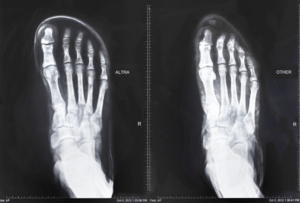

For those of you who’re browsing our blog from work, I’ll spare you the gore: I have extremely strange feet. They’re very wide, completely flat, and connected to ankles that bow inward. When I get out of the pool and step on the pavement, I leave a giant footprint; there’s no curve to it whatsoever – only a big, ugly plank.

When I first put them on, it just made sense: Altras are the first shoe that fit my feet comfortably. The wide toe box gives my feet ample breathing room, especially during the dreaded long-run swelling. I ramped up to making them my everyday shoe by alternating runs with my old shoes. Only weeks after my first run, I posted a PR 12K at Bay to Breakers, and wore them for the marathon leg of Ironman Lake Placid.

Since then, I’ve gone on to buy four more pairs in the past calendar year: Torins for road running, 3-sums for triathlon and speed work, Lone Peak 1.5s for trail running, and Instinct 1.5s as a replacement to the Torins’ (after hundreds of quality miles!). Each shoe follows the same core design principle – zero drop, which means that there’s no difference between the height of the heel and the forefoot.

Zero drop proponents will tell you that keeping the forefoot and heel on the same plane results in increased stability, less impact, and proper running technique. I’ve noticed a major improvement to my cadence since making the switch, and I now emphasize driving with my glutes and hips more than I did in a conventional running shoe. To be clear, I’m by no means advocating zero drop for everyone – it works for me, and I’ve reaped the benefits of running in a similar shoe on both the road and the trail.